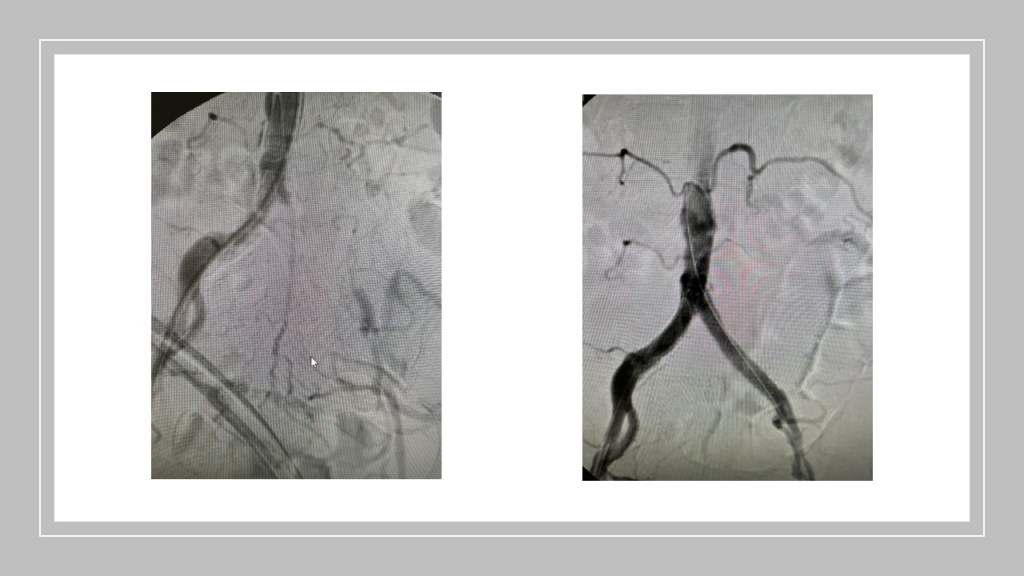

Eröffnung und Stentimplantation der ursprünglich verschlossenene Aorta und Beckengefäße.

Der Patient kann das Krankenhaus am selben Tag oder nach einer Übernachtung wieder verlassen.